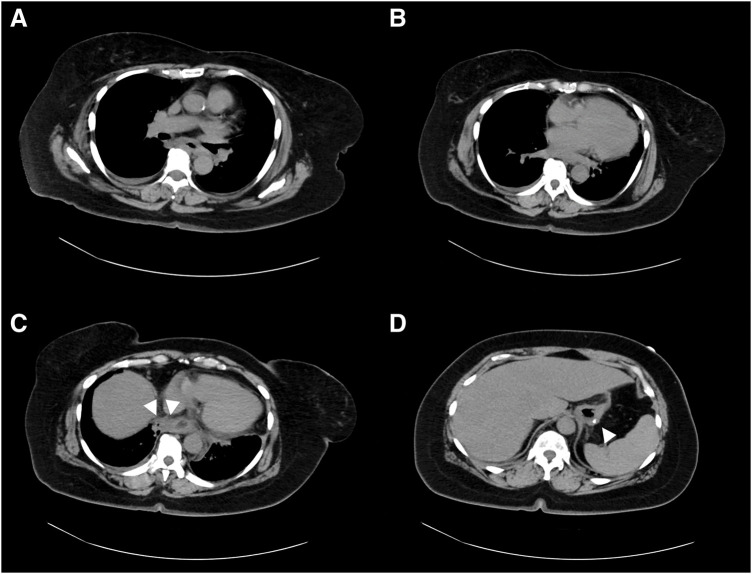

Case presentation: A female patient with morbid obesity (body mass index, 41 kg/m2) and a heavy smoking habit underwent laparoscopic sleeve gastrectomy and was discharged without any immediate postoperative complications. Six weeks later, the patient presented with severe chest and back pain that required continuous fentanyl injection for pain management. Initially, staple line leakage, commonly observed after sleeve gastrectomy, was suspected. However, her condition progressively worsened, and she was admitted to the ICU. An enhanced abdominal CT scan extending to the cervical region revealed a cervical abscess extending to the lower mediastinal region. The patient was diagnosed with descending necrotizing mediastinitis. Given the rarity of this disease, we hypothesized that her smoking habits exacerbated the piriform fossa injury caused by the calibration tube used during gastrectomy. Following the diagnosis, emergency abscess drainage surgery was performed, and the patient was successfully treated.

Conclusions: This is the 1st reported case of descending necrotizing mediastinitis as a fatal complication of laparoscopic sleeve gastrectomy, which was identified and treated successfully owing to the timely and expanded use of an enhanced CT scan that included the cervical region. Traditionally, the cervical area has not been routinely examined when diagnosing complications following abdominal surgery, underscoring the importance of a comprehensive imaging approach from the neck to the abdomen to detect complications after sleeve gastrectomy.